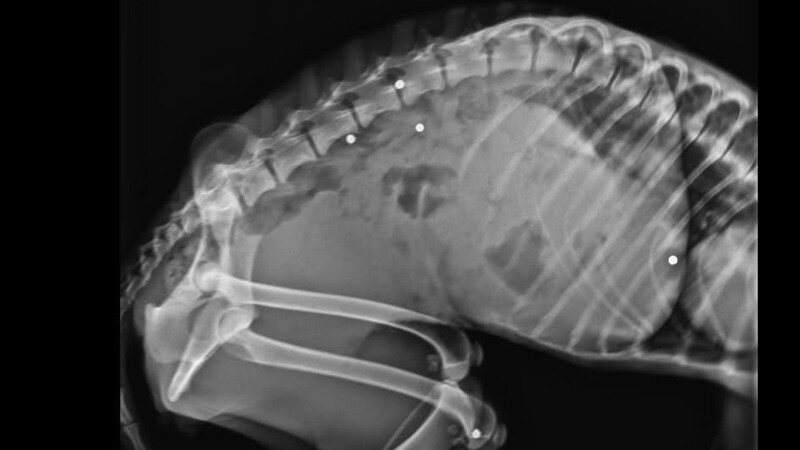

Our team has made a devastating discovery - Bilochka has been shot several times. This, coupled with a severe kidney infection that has claimed one of her kidneys, has left her in a critical condition. She now urgently requires blood transfusions and possibly surgery to remove the bullets, procedures that are costly and challenging for our partner rescuers in Ukraine.

P.S. We've recently discovered that Bilochka has been shot multiple times and she urgently needs blood transfusions. This is a critical time for her, and we need your help. Please donate now. Your gift could be the lifeline Bilochka desperately needs.